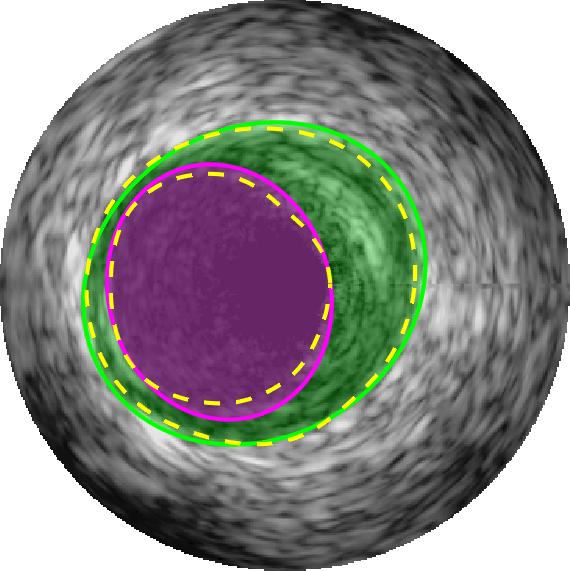

Qualitative evaluations are illustrated in Figure 4 and show the successful segmentation results of the proposed EREL selection strategy for 20 IVUS frames. The lumen areas are highlighted by the magenta colour while the media regions are green. Also, the manually annotated contours for both lumen and media are drawn as yellow dashed lines. As we can see, the chosen frames contain a variety of lumen and media morphologies.